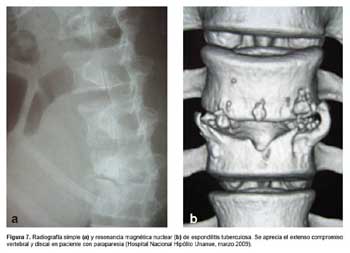

Tuberculosis: diversas manifestaciones de una misma enfermedad

Tradicionalmente se ha definido a la sífilis como la gran simuladora de las enfermedades infectocontagiosas, sin embargo la tuberculosis es igual de proteiforme en cuanto a sus manifestaciones clínicas. Esto se debe, entre otras causas, a tres factores importantes.

El primero, su capacidad de diseminación por vía hematógena y linfática. Esto le confiere la facultad de alterar la morfología y funcionamiento de virtualmente todos los órganos del cuerpo humano, incluso muchos años luego de la primo-infección, debido a su habilidad para permanecer latente en los mismos.

Estas manifestaciones atípicas de tuberculosis, tan variables, deben generar sospecha en el personal de salud, siendo una enfermedad muy prevalente en nuestro medio. Debemos recordar que ante un cuadro clínico raro, es más probable la manifestación atípica de una enfermedad frecuente que la manifestación típica de una enfermedad infrecuente.

Todo médico peruano debe conocer a fondo, no sólo la clásica radiografía de tórax con infiltrado apical o caverna, tan representativas de esta condición, sino también debe estar atento a solicitar las pruebas pertinentes ante posibles cuadros raros de esta enfermedad, que sin ninguna duda en los próximos años seguiremos viendo frecuentemente en los consultorios y salas de nuestros hospitales.